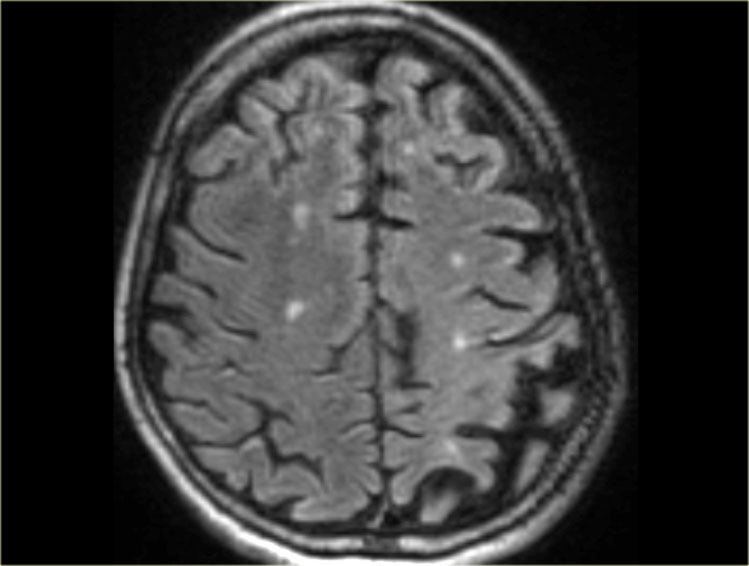

Fazekas scale for WM lesions

On MR, white matter hyperintensities (WMH) and lacunes - both of which are frequently observed in the elderly - are generally viewed as evidence of small vessel disease.

The Fazekas-scale provides an overall impression of the presence of WMH in the entire brain.

It is best scored on transverse FLAIR or T2-weighted images.

Score:

• Fazekas 0: None or a single punctate WMH lesion

• Fazekas 1: Multiple punctate lesions

• Fazekas 2: Beginning confluency of lesions (bridging)

• Fazekas 3: Large confluent lesions

The Fazekas scale for WM lesions predicts future disability in elderly. The Fazekas scale for WM lesions predicts future disability in elderly.

Fazekas 1 is considered normal in the elderly.

Fazekas 2 and 3 are pathologic, but may be seen in normally functioning individuals.

They are however, at high risk for disability.

In 600 normally functioning elderly people the Fazekas score predicted disability within one year (table). In the Fazekas 3 group 25% was disabled within one year (10).

Three year follow-up shows that severe white matter changes independently and strongly predict rapid global functional decline (17).